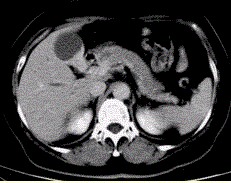

问题 患者女,50岁,右上腹痛,向肩胛部放射,伴有消瘦、乏力。查体:皮肤巩膜黄染,墨菲(Murphy)征阳性。CT示胆囊壁不规则增厚(下图)。 最可能的诊断为

选项 A.胆囊炎 B.胆囊结石 C.胆管炎 D.胆囊癌 E.胆囊腺肌症

答案 D